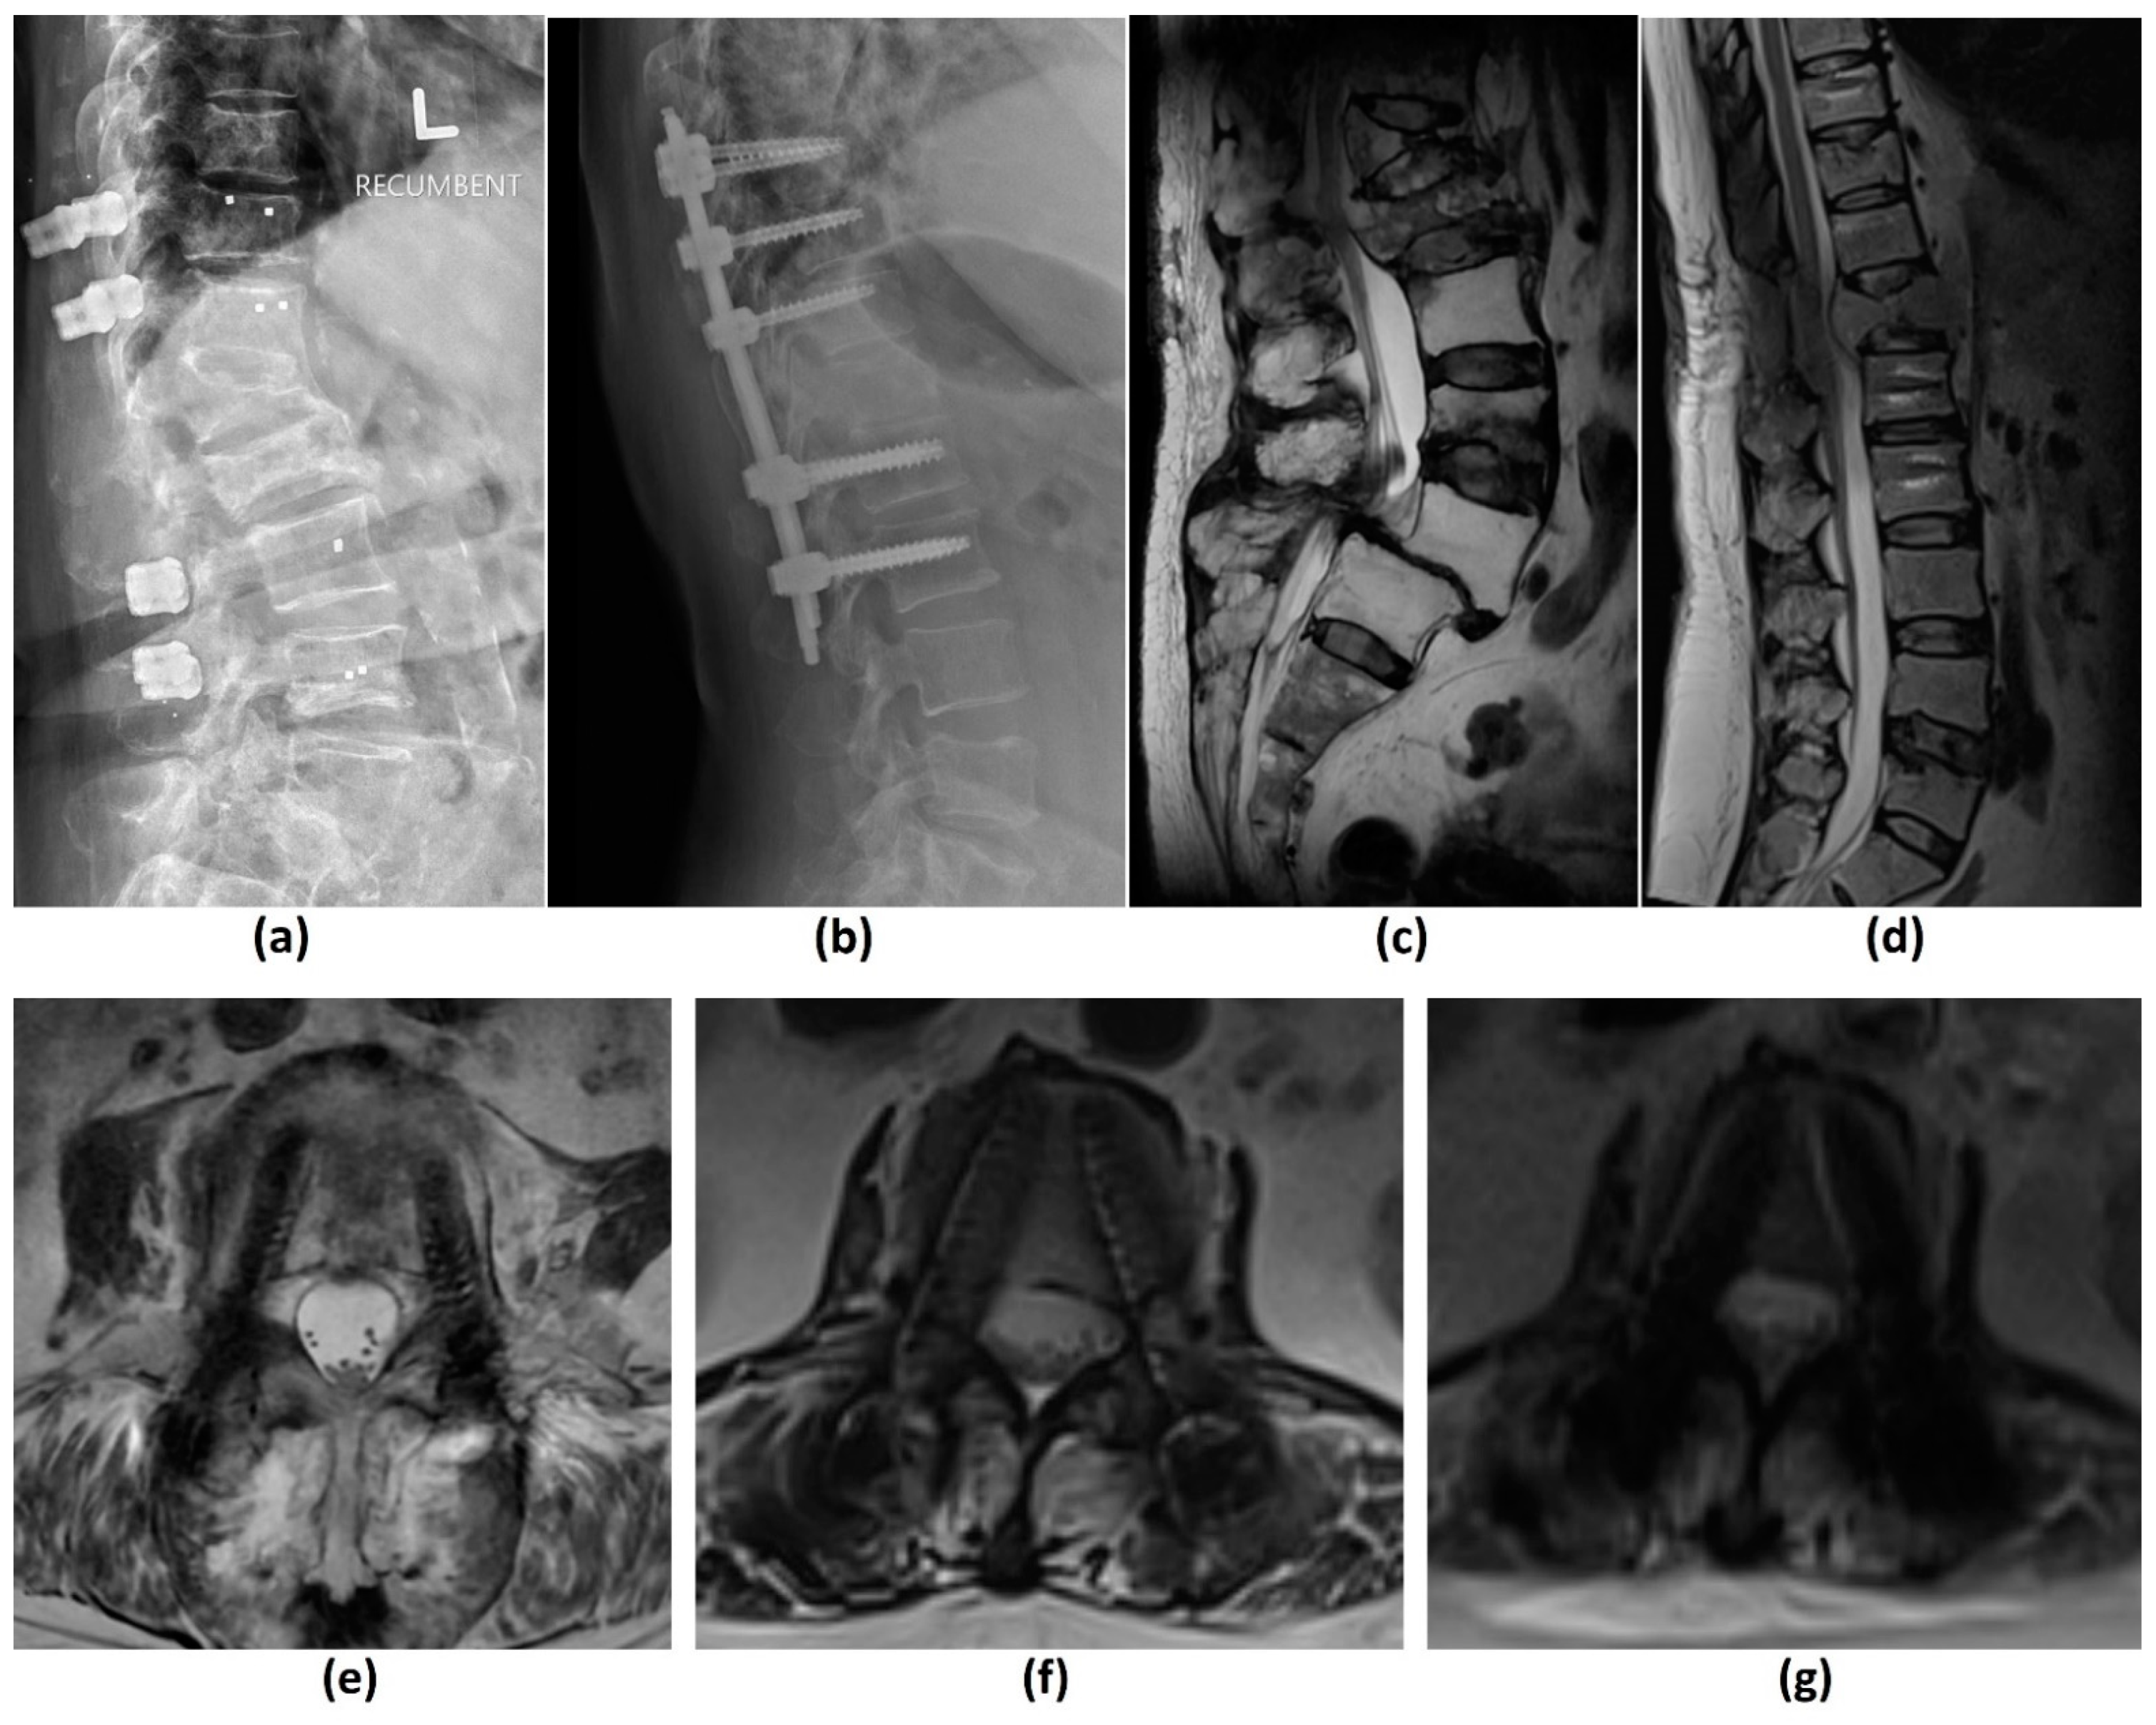

3.3. Computed Tomography (CT) Myelogram

- MRI is contraindicated (e.g., due to extreme claustrophobia, large body habitus, inability to lie still for a prolonged period of time, metallic foreign body in orbit, or a noncompatible cardiac device);

- Poor diagnostic yield of MRI due to metal artifacts from spinal implants (CT will also require MAR techniques);

- Stradiotti, P.; Curti, A.; Castellazzi, G.; Zerbi, A. Metal-related artifacts in instrumented spine. Techniques for reducing artifacts in CT and MRI: State of the art. Eur. Spine J. 2009, 18 (Suppl. 1), 102–108. [Google Scholar] [CrossRef]

- Do, T.D.; Sutter, R.; Skornitzke, S.; Weber, M.A. CT and MRI Techniques for Imaging Around Orthopedic Hardware. Rofo 2018, 190, 31–41. [Google Scholar] [CrossRef] [PubMed]

- Katsura, M.; Sato, J.; Akahane, M.; Kunimatsu, A.; Abe, O. Current and Novel Techniques for Metal Artifact Reduction at CT: Practical Guide for Radiologists. Radiographics 2018, 38, 450–461. [Google Scholar] [CrossRef] [PubMed]

- Huber, F.A.; Sprengel, K.; Müller, L.; Graf, L.C.; Osterhoff, G.; Guggenberger, R. Comparison of different CT metal artifact reduction strategies for standard titanium and carbon-fiber reinforced polymer implants in sheep cadavers. BMC Med. Imaging 2021, 21, 29. [Google Scholar] [CrossRef]